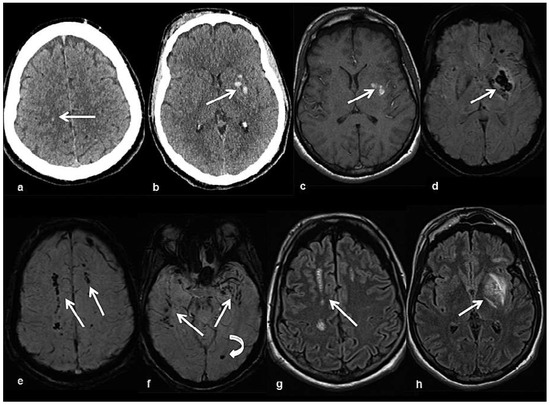

Head and brain trauma: general aspects and neuroimaging

by Johanna Maria Lieb, Christoph Stippich and Meritxell Garcia

Swiss Arch. Neurol. Psychiatry Psychother. 2015, 166(8), 279-292; https://doi.org/10.4414/sanp.2015.00374 - 1 Jan 2015

In this article the general clinical aspects, imaging indications and different injury mechanisms of traumatic brain injury (TBI) are reviewed. In addition, the different imaging modalities and strategies are presented, including more specific imaging features of the various injuries. Computed tomography (CT) is the imaging modality of choice in the acute phase owing to its wide availability and short scanning time, as well as to its high sensitivity for the detection of fractures and acute bleeding. Although magnetic resonance imaging (MRI) is superior to CT in many other aspects, it plays no role in the acute phase. MRI, however, has been proven to be useful and complementary to CT in the subacute and chronic stages as well as in the case of inconclusive results on initial CT. Especially the use of standard sequences like fluid attenuated inversion recovery (FLAIR), diffusion and susceptibility weighted imaging (DWI and SWI) have been shown to increase the diagnostic potency in diffuse axonal injury, in mild brain trauma and also in more chronic stages of TBI. The use of more advanced MRI techniques such as diffusion tensor imaging (DTI), magnetic resonance spectroscopy (MRS), functional MRI (fMRI) and magnetic transfer imaging (MTI) can further complete the diagnostic evaluation and give insights into different pathophysiological processes in TBI. Full article